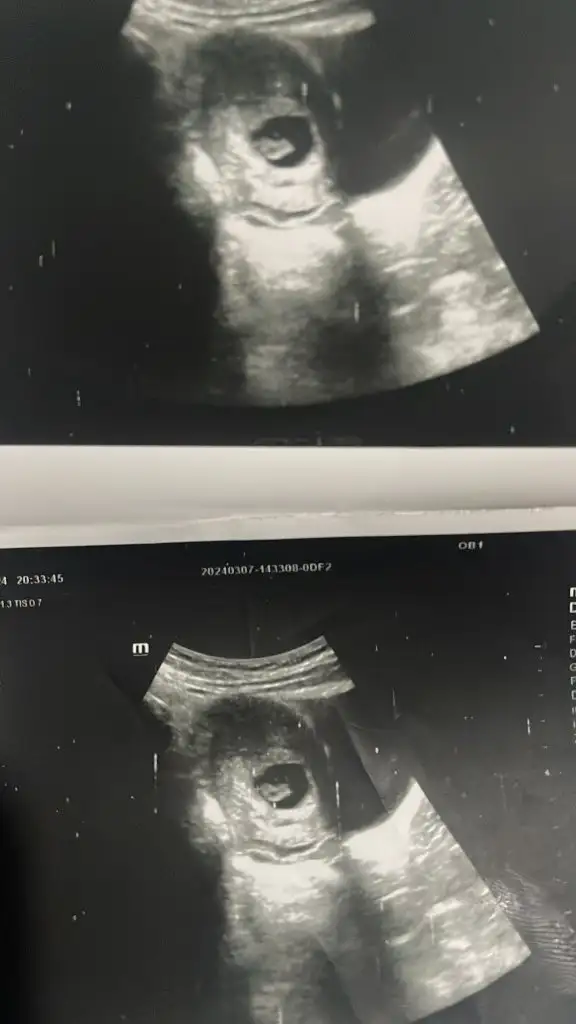

Şuan 9+1 olduk ama bu ultrason 7+4 iken çekildi. Bakalım cikacakmi çok merak ediyorum.